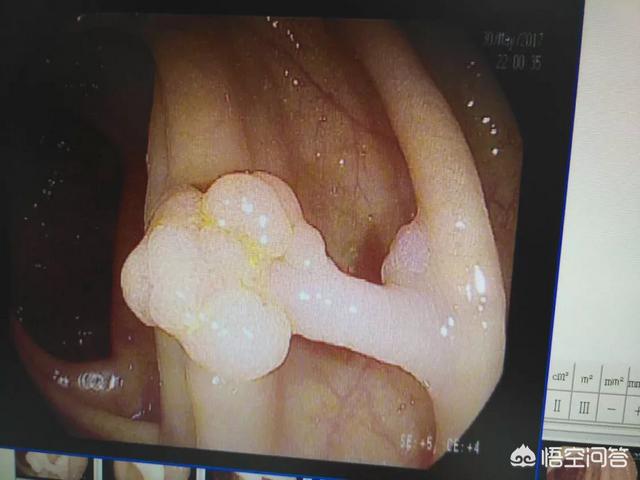

配图是我做过的一个肠道良性的息肉,最后切下来病理报告不是恶性的肿瘤!